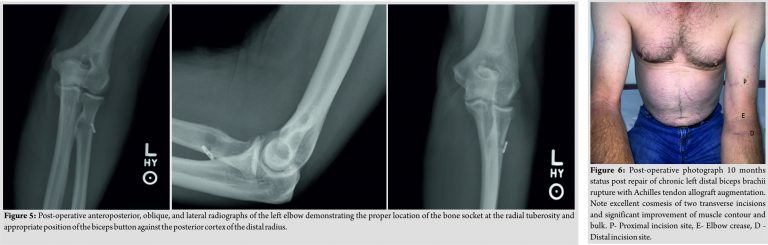

Our preferred technique involves exposure and preparation of the radial tuberosity through a volar transverse incision, followed by location of the biceps tendon stump through a second, more proximal transverse incision, suture of Achilles tendon allograft proximally, and finally, tensioning and fixation of the allograft to the radial tuberosity with a trough and cortical button. The patient was positioned supine with his left elbow extended on a hand table. After prepping and draping, a well-padded sterile tourniquet was wrapped as proximally as possible around the left upper arm and after Esmarchexsanguination of the arm was inflated to a pressure of 250 mmHg. Under 2.5x loupe magnification, a transverse 2.5 cm incision was made on the volar aspect of the forearm, 3.5 cm distal to the flexion crease of the left elbow, in line with the expected location of the radial tuberosity. The deep fascia of the forearm was identified and incised, exposing the interval between the brachioradialis radially and the pronator teres ulnarly. Branches of the lateral antebrachial cutaneous nerve identified proximally overlying the brachioradialis were mobilized laterally and protected. Blunt digital dissection was used to facilitate the development of the interval. The brachioradialis was retracted laterally using a lateral retractor and the pronator teres medially using an army-navy retractor. The location of the radial tuberosity was confirmed by digital palpation while the forearm was pronated and supinated. After this was done, soft tissues consisting of remnants of the biceps tendon stump and periosteum were elevated using a blunt periosteal elevator to fully expose the bony radial tuberosity. Remnants of degenerated tendon and periosteum were excised with a rongeur. Once the radial tuberosity had been fully exposed, a moist sponge was placed into the woud and attention was turned to locating the biceps tendon stump. The biceps muscle was palpated proximal to the antecubital fossa. A transverse incision was made at the approximate location of the musculotendinous junction. The muscle belly of the biceps was found to be significantly scarred proximally. The biceps tendon was encased in firm scar tissue with appeared to be in continuity with the deep fascia of the arm and remnants of the lacertusfibrosus. After dissection, only minimal native biceps tendon was able to be identified, extending for only 1–2 cm distal to the biceps brachii muscle belly.An Allys clamp was then placed on the retracted stump. The biceps brachii was then meticulously dissected free from scar tissue circumferentially to facilitate maximal excursion and the Allys clamp was then used to deliver the biceps out of the proximal wound (Fig. 2).A fresh-frozen Achilles tendon allograft (Allosource, Centennial, CO) measuring 16.5 cm × 1.2 cm was then thawed and the calcaneal bone block removed. The necessary graft length was estimated by laying the graft across the biceps muscle with the fan-like portion of the graft proximal and the tendinous portion located distally. We prefer to suture the allograft to the native biceps muscle-tendon unit proximally and estimate tension and necessary graft length with the elbow in approximately 45° of flexion before distal fixation into the radial tuberosity. After estimating appropriate tension, the distal tendinous portion of the graft was trimmed such that the length was felt to be appropriate to reach the radial tuberosity, and the distal 2 cm of the graft passed easily through a 7-mm cylindrical graft sizer.The proximal fan-like portion of the graft was then sutured to the biceps brachii with interrupted No. 2 Fiber wire sutures (Athrex, Naples, FL) (Fig. 3). Buried horizontal mattress sutures were placed through the center of the biceps to secure the central portion of the graft to the native biceps to add strength to the construct. Once the graft was secured proximally, manual traction was placed on the distal end of the construct to evaluate strength. No tearing of either the graft or the biceps was observed to occur. A Fiberloop suture (Arthrex, Naples FL) was then placed through the distal portion of the allograft tendon such that the two free ends of suture exited the distal end of the tendon. A line was marked on the allograft tendon 1 cm from the end to help visualize the tendon docking into the radial tuberosity. A Biceps Button (Arthrex, Naples, FL) was then attached to the free ends of the suture. One limb of suture was passed through one side of the Biceps Button and back through the opposite side. The other suture limb was threaded through the button in the same manner, starting on the opposite side as the first suture limb. Care was taken to ensure that the suture limbs were not tangled by placing tension on each of the sutures such that the button slid freely on the sutures. The allograft was then retrieved through the proximal incision, tunneled in a subcutaneous fashion distally and retrieved through the distal incision (Fig. 4). Retractors were then replaced in the distal wound to visualize the radial tuberosity. The arm was placed in maximal supination to protect the posterior interosseous nerve, which also brought the tuberosity directly into view. A 2.7 mm spade-tipped guide wire was then drilled into the center of the radial tuberosity through both the anterior and posterior cortex. A 7.5 mm acorn reamer was then used to ream only the anterior cortex to create a bone socket for placement of the allograft tendon.The size of the reamer selected was purposely slightly larger then the circumference of the tendon graft to accommodate later adjunctive fixation with an interference screw. Bony debris was meticulously removed using lavage and irrigation. The biceps button was then passed through the posterior cortex of the radius under direct visualization. With the elbow in 45° of flexion, the two free ends of the suture attached to the button were then tensioned, allowing the button to “flip” against the posterior cortex of the radius and advancing the Achilles allograft into the radial tuberosity. Using an arthroscopic knot pusher, sequential square knots were tied against the posterior cortex of the radius. A 7mm × 10 mm PEEK interference screw (Arthrex, Naples, FL) was then placed into the trough adjacent to the tendon to provide adjunctive fixation. The elbow was then ranged and the repair was stable from 30 to 130° of elbow flexion and through full pronation and supination. The wounds were copiously irrigated before release of the tourniquet. After hemostasis was achieved, subcutaneous closure was performed with 2–0 vicryl suture and both transverse skin incisions were closed with running subcuticular 4–0 Prolene. The patient was placed into a long-arm fiberglass posterior splint with the elbow at 90° of flexion and neutral forearm rotation. No drains were utilized. Post-operative neurovascular exam revealed no deficits. The splint and sutures were removed on post-operative day 10 and the patient was placed into a hinged elbow brace with an extension block at 30°. Post-operative radiographs confirmed the location of the bone socket at the location of the radial tuberosity as well as the position of the biceps button against the posterior cortex of the proximal radius (Fig. 5).A supervised physical therapy program was initiated that permitted passive and active-assisted ROM and which gradually advanced the patients elbow extension. Resisted motion and strengthening were initiated 3 months after surgery. At 5 months after surgery, the patient was returned to modified work duties consisting of a 5-pound weight restriction on the left arm. He continued to progress with strengthening and at 9 months after surgery was returned to his regular duties as a cabinetmaker. Although he still reported some slight weakness in the left arm compared to the right, he was subjectively satisfied with the outcome of the surgical procedure and indicated that he would choose to have the same operation performed again. At 10 months after surgery, his active ROM was 0–135 of elbow flexion and 90 of pronation and supination. Maximal resting biceps circumference was improved to 31.5 cm on the left side compared to 32.5 cm on the right side. Post-operative MEPI score was 100 compared to pre-operative score of 65. With the MEPI scoring system, a lower score indicates higher disability. The post-operative DASH disability/symptom score was 2.5, compared to a preoperative value of 15.Post-operative DASH work module score was 12.5 compared to 100 preoperatively. With the DASH scoring system, a higher score indicates higher disability. The patient’s preoperative DASH work module score indicates that the patient was unable to perform any of his work-related activities before the surgical procedure, whereas postoperatively he was able to return to work with minimal symptoms. Post-operative incisions were cosmetic and muscle contour was significantly improved compared to pre-operative status (Fig. 6).